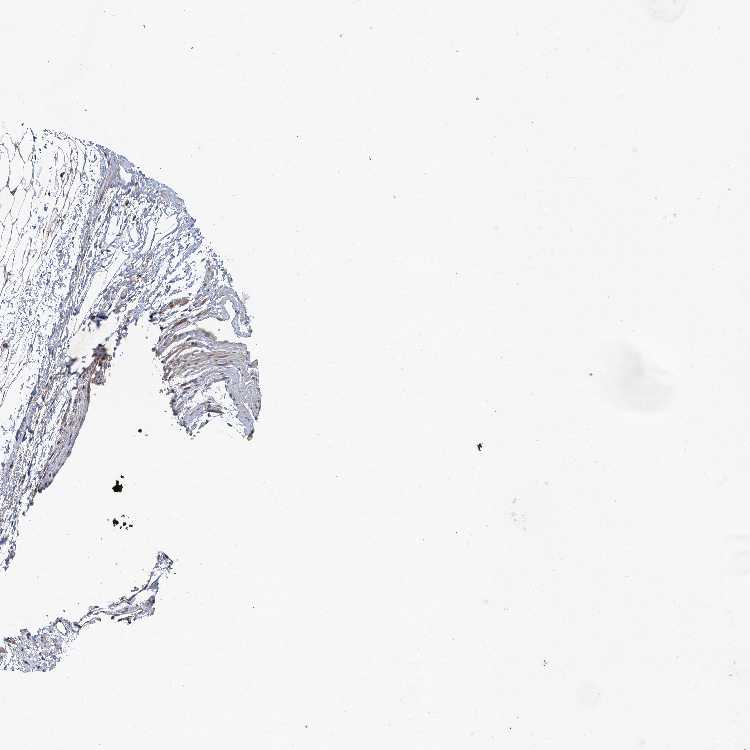

SOFT TISSUE 1 - Antibody stainingi

Antibody staining in the annotated cell types in the current human tissue is reported as not detected, low, medium, or high, based on conventional immunohistochemistry profiling in selected tissues. This score is based on the combination of the staining intensity and fraction of stained cells.

Each image is clickable and will lead to virtual microscopy that enables deeper exploration of all samples and also displays staining intensity scores, fraction scores and subcellular localization as well as patient and tissue information for each sample.

Antibody HPA037700Antibody HPA037701

Chondrocytes -Medium

Fibroblasts Not detectedLow

Peripheral nerve Medium-